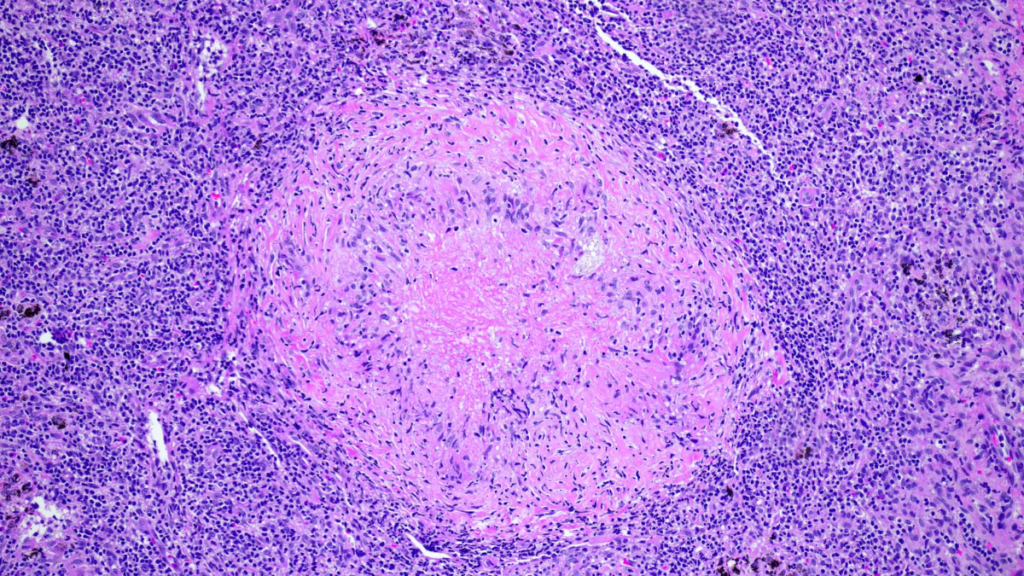

B. Powstawanie martwicy i jej konsekwencje

W wyniku reakcji zapalnej i uszkodzenia ścian jelit dochodzi do powstawania obszarów martwicy w tkance jelitowej. Martwica oznacza śmierć komórek i tkanek, co prowadzi do dalszego pogłębiania uszkodzeń w jelitach. Martwica może prowadzić do perforacji jelit, co z kolei zwiększa ryzyko wycieku treści jelitowej do jamy brzusznej i wywołania groźnych powikłań, takich jak zapalenie otrzewnej czy sepsa.

C. Rola bakterii w procesie zapalnym

Bakterie odgrywają istotną rolę w procesie zapalnym towarzyszącym martwiczemu zapaleniu jelit. W normalnych warunkach bakterie obecne w jelitach odgrywają pozytywną rolę w procesach trawiennych i funkcjonowaniu układu odpornościowego. Jednak w przypadku martwiczego zapalenia jelit, obecność nadmiernych ilości bakterii, zwłaszcza tych patogennych, w obszarach uszkodzonych jelit, przyczynia się do nasilenia procesu zapalnego i pogarszania stanu pacjenta. Ponadto bakterie mogą przyczyniać się do tworzenia toksyn, które dodatkowo uszkadzają tkanki jelitowe i nasilają proces martwicy.